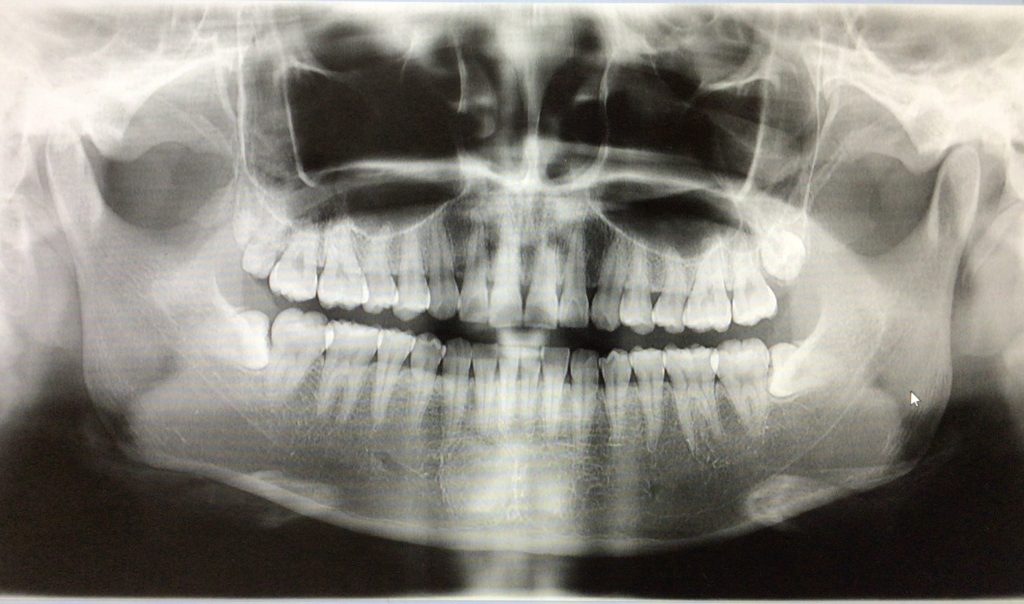

親知らずの抜歯について‥‥

予約したその日に1本ずつでも4本同時抜歯も可能です!主治医の先生にご相談ください